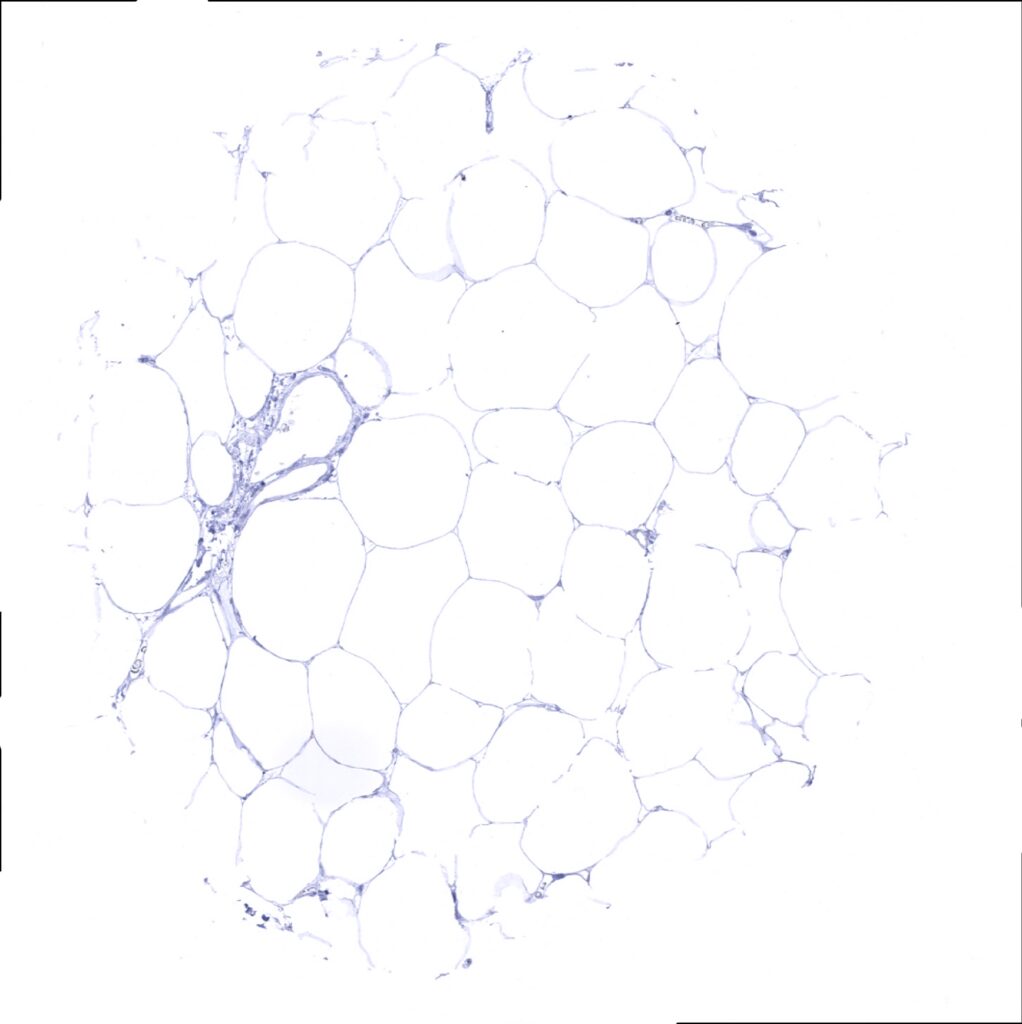

E-Cadherin antibody [MSVA-035R] HistoMAX

Fat